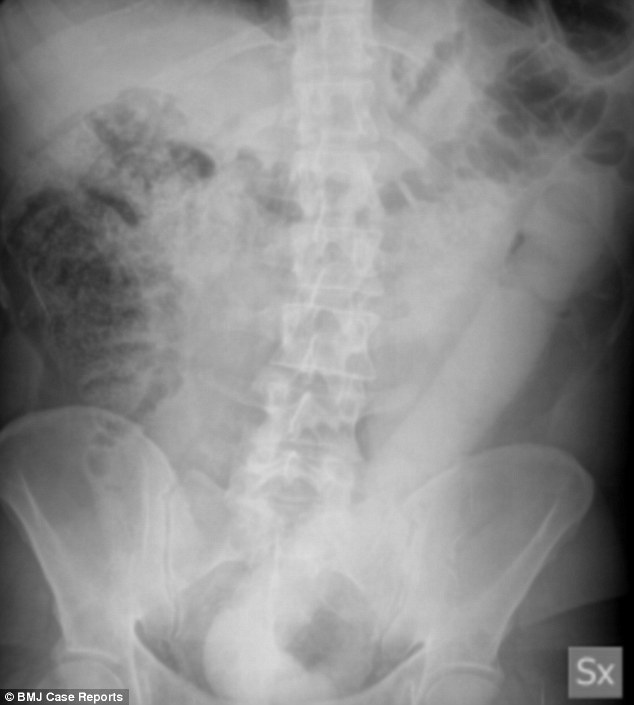

Baffled doctors were forced to invent a lasso-like tool to remove a 23-inch (60cm) dildo firmly lodged inside a man.

The concerned 31-year-old, from Italy, went to hospital after he couldn’t remove the massive sex toy, which had been stuck for 24 hours.

Medics in Milan were unable to get the rubber dildo out using standard methods, complaining it was too big and smooth.

Consultants then referred him to the hospital’s endoscopy unit, to allow surgeons the chance of removing the dildo.

Writing in the journal, medics led by Dr Lorenzo Dioscoridi said: ‘Several standard attempts with different extraction devices were made.’

A 50mm polypectomy’s snare – a wire loop device used to chop off abnormal tissue growths called polyps – was also ineffective.

Dr Dioscoridi and colleagues said the technique didn’t work because of the ‘rigidity, the smoothness and the large size of the foreign body’.

Forceps and a wire-guided dilation balloon – another common method – failed because of the ‘hard consistence’ of the dildo.

Usually, surgery is the only remaining option to remove foreign bodies that are stuck. But the new technique may change that.

After all their attempts, the medics built a ‘home-made’ snare, designed to hook onto the dildo and drag it back out of the man’s rectum.

In the journal they wrote: ‘We finally succeeded in the endoscopic extraction of the device, catching the distal edge of the dildo with this guidewire lasso.

‘This device showed a technical advantage as compared with ordinary polypectomy snares, due to its much higher stiffness.’

Dr Dioscoridi said this made it possible to detach the colonic wall from the dildo and ‘effectively pull the object’.

The medics said the new technique may be a ‘valid option’ to remove large foreign bodies from the colon and rectum when standard methods for extraction fail.